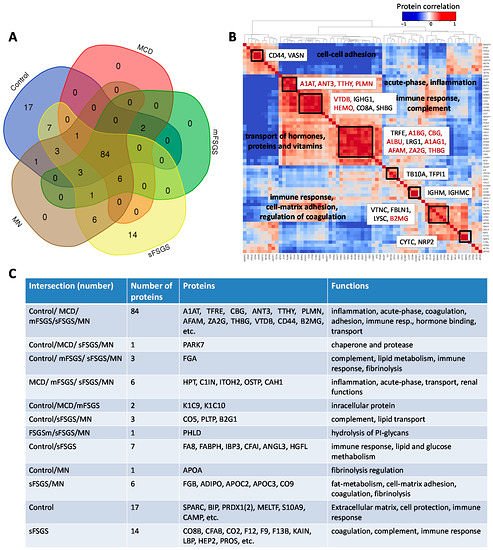

Распределение 138 белков из анализа BAK270 MRM, которые были идентифицированы в 69 образцах мочи здоровых пациентов и пациентов с ХБП и гломерулопатиями: (A) Диаграмма Венна для белков, идентифицированных в ≥2/3 образцов по крайней мере от одной группы пациентов. (B) Парные корреляции между основными белками. (С) Описание белков в соответствии с их распределением на схеме.